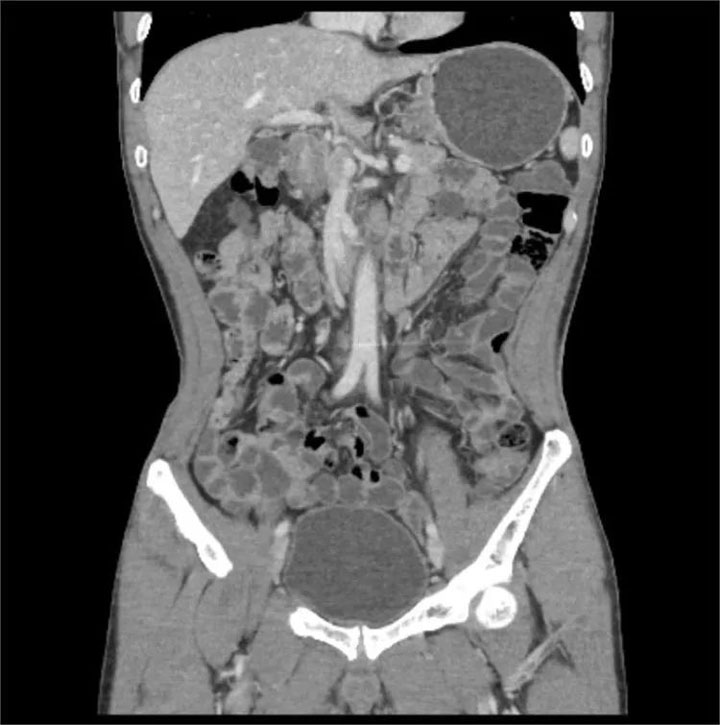

CT小肠造影(CT enterography,CTE)是患者口服或经小肠导管注入对比剂使小肠腔充盈足量对比剂后,经多排螺旋CT增强扫描,并将图像进行后处理,使肠腔、肠壁、肠系膜、腹腔内血管、后腹膜及腹内实质脏器多方位显示出来的技术。临床证明,CT小肠造影(CT enterography,CTE)可精确的判定小肠肿瘤的数目,监测出小肠早期肿瘤,可作为小肠肿瘤定位及诊断的首先检查方法。

CTE简便易行,无明显并发症,不仅能观察肠腔、肠壁、肠外淋巴结、肠系膜、肠系膜血管关系以及毗邻结构等,还可以精确显示粘膜病变、肠壁增厚及肠外并发症,可准确判断小肠肿瘤的浸润深度。适用于多种小肠病变,全腹部扫描能及时发现肿瘤转移情况,有助于临床更准确的把握肿瘤术前分期,能够为患者制定最优治疗方案,带来更好的预后。